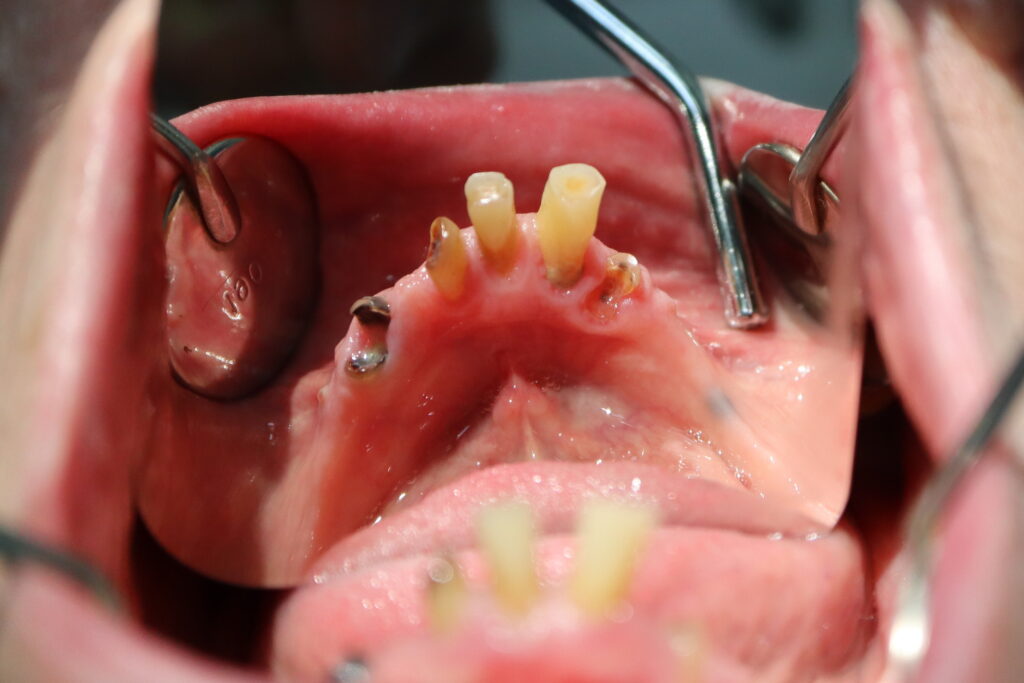

На верхней и нижней челюстях были удалены зубы и проведена комплексная имплантация по системе All-on-4, установлены 8 имплантатов Osstem.

процесс имплантации

Это фото может содержать тяжелый для восприятия контент